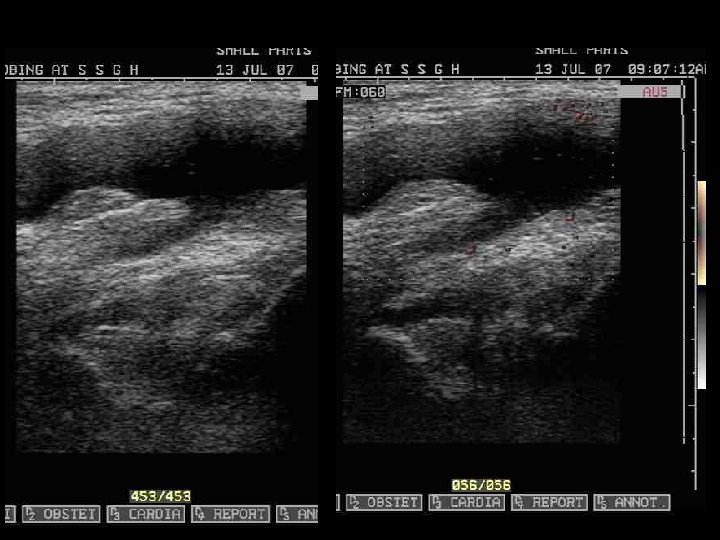

• 25 years old female. • H/O Primary infertility, referred for pelvic ultrasound. • No other complaints. • Past & family histories are not significant. • P/V : NAD

prominent fundal cleft with persistently seperated upper uterine segment with partial fusion of lower uterine segment.

Diagnosis • Uterus bicornis unicollis

Class IV (bicornuate uterus) • A bicornuate uterus results from partial nonfusion of the müllerian ducts. • On US: – demonstrate 2 uterine cavities with normal endometrium. – a concave fundus with a fundal cleft greater than 1 cm. This has been shown to be a reliable means of distinguishing bicornuate from septate uteri. – An increased intercornual distance (>4 cm) may be observed. – The septum separating the 2 horns demonstrates echogenicity identical to that of myometrium. • On MRI : – The tissue separating the 2 horns demonstrates signal intensity identical to myometrium on all pulse sequences.

Bicornuate uterus. Schematic diagram shows the partial fusion of the lower uterine segment and persistently separated upper uterine segments with a prominent fundal cleft (>1 cm). On hysterosalpingography films, shows the widened intercornual distance (>4 cm) and the widened intercornual angle (>60°)

In the bicornuate uterus if the central myometrium extend to the level of the internal cervical os its results in bicornuate unicollis uterus